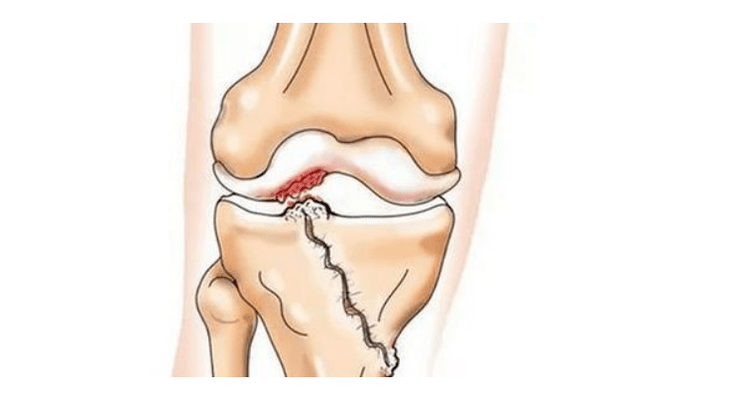

- Blessures (fractures, ménisque déchiré et ligament croisé antérieur). Malheureusement, ces blessures provoquent un stress excessif sur le cartilage chez chaque personne, quel que soit son âge. Une fracture d'une partie de l'os recouverte de cartilage s'accompagne de la formation d'une irrégularité - une « marche ». Dans cette zone, l'abrasion et l'arthrose surviennent avec le mouvement ;

Dans l'arthrose (arthrose), outre la destruction progressive du cartilage, la perte de son élasticité et de ses propriétés d'amortissement, les os sont également progressivement impliqués. Sous l'effet du stress, des arêtes vives (exostoses) apparaissent, qui sont considérées à tort comme des « dépôts de sel » – dans l'arthrose classique, il n'y a pas de dépôt de sel. Au fur et à mesure que l’arthrose progresse, elle continue de « manger » le cartilage. Ensuite, l’os se déforme, des kystes se forment, toutes les structures de l’articulation sont touchées et la jambe se plie.

Manque de cartilage dans la plupart des zones touchées, sclérose (durcissement) sévère de l'os, nombreux ostéophytes et rétrécissement ou absence sévère de l'espace articulaire. La douleur est quasi constante et la démarche est altérée. La mobilité est sévèrement restreinte et des déformations articulaires importantes se produisent. Les AINS, la physiothérapie et les autres méthodes standard de traitement de l'arthrose du genou sont inefficaces.